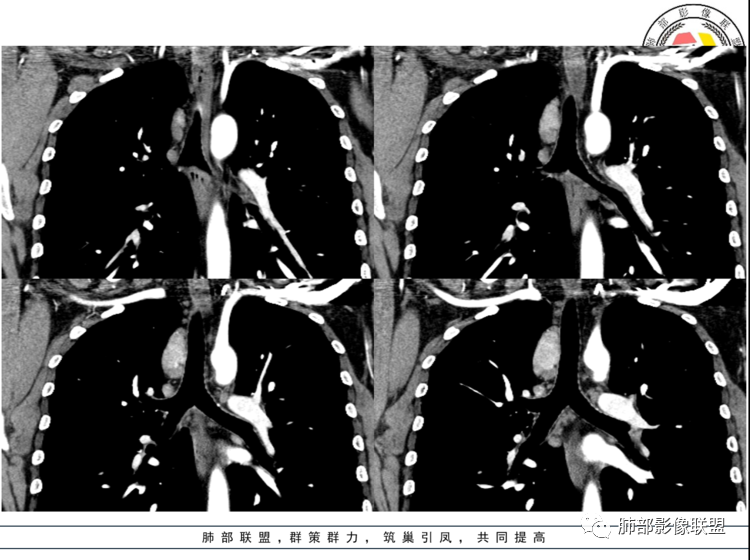

男,40岁,体检发现纵隔占位

•查血常规、血生化、肿瘤标志物、尿常规大致正常。气管腔静脉间隙团块状影,密度均匀,边界清楚,增强扫描,明显的强化,肿块的周围气管旁见多个肿大的淋巴结,强化特点类似。考虑良性占位,巨淋巴增生症。需要与异位胸腺瘤、结节病、淋巴瘤、副神经节瘤、淋巴结转移瘤鉴别。

患者中年男性,体检发现纵隔占位。胸部CT:右上前纵隔不规则占位灶,位于上腔静脉后方,血管无推移,边缘光滑,密度均匀,增强动脉期明显强化,综合考虑良性病变,巨大淋巴结增生症可能大。鉴别神经源性肿瘤。

右前中纵隔软组织肿块,有钻缝生长特点,边界清,周围脂肪血管未见受侵,增强动脉期明显强化,明显持续强化,内部及周围见血管,周围见小淋巴结,考虑CD,鉴别淋巴瘤,强化不支持;胸腺瘤,不常见部位,形态也不支持;副节瘤,这么大肿块坏死囊变应很明显;神经内分泌肿瘤,强化太均匀、生化不支持,周围结构改变也不符合;神经鞘多有AB区,渐进性强化!

中纵隔内类椭圆形软组织占位,密度均匀,边界清晰,与周围结构分界清晰,腔静脉向外推移,周围见数个增大淋巴结,增强扫描明显均匀性强化,考虑良性,CD可能性大,鉴别神经源性肿瘤。

定位,中纵隔,上腔静脉向前推移。椭圆形软组织影,边界清晰,密度均匀,周围脂肪间隙清晰。增强明显均匀强化。

考虑,良性,CD,鉴别副节瘤。

动脉期显著强化,结节呈“门状结构”附近多发子灶——CD!

3.1单发型CD的肺部表现

单发型CD多为透明血管型,所以明显强化和中央分枝状钙化具有特征性。在CT上表现圆形或类圆形软组织密度影,伴或不伴周围淋巴结增生,体积一般较大,边缘光整,病灶中央的弧形、线样、分枝样及枯枝样钙化(因为肿块内增生的血管组织玻璃样变或退变后钙盐沉积,故多呈血管样铸型的分支状或枯枝状);透明血管型因为其内血供丰富,周围可见粗大的供血动脉,在多期扫描动脉早期明显强化,强化程度与大血管相仿,又由于病灶内血管壁玻璃样变或纤维化及内皮细胞过度增生致血管腔狭窄,对比剂退出减慢,故延迟扫描扫描仍可持续强化,呈“早进晚出”的强化方式。因为其血供丰富,坏死、囊变或出血少见,但是有时候病灶内灶状或条片状低密度影,是纤维组织或发生玻璃样变性的血管结构,而不是缺血坏死区。